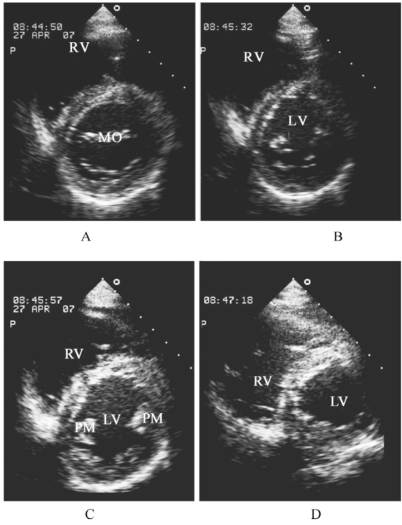

1.14.2.3三、室壁节段划分方法

-